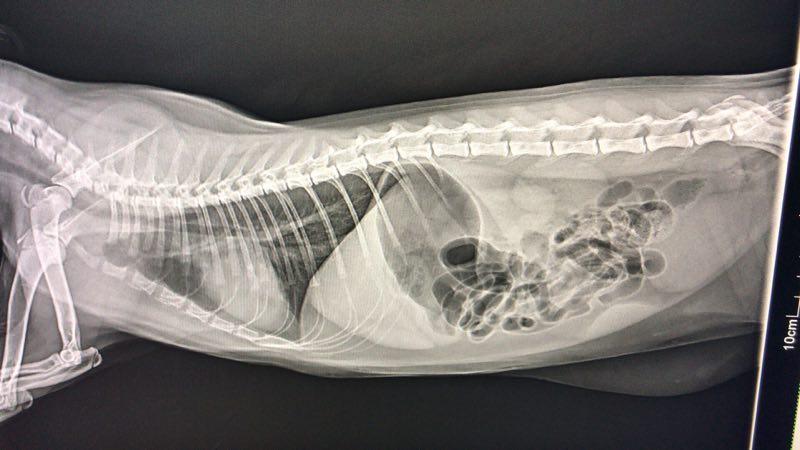

一般给猫咪做胸部X光检查和血常规来确定猫咪是否肺炎。也可通过超声波来检测肺部的感染。

▲感染肺炎的x光

▲未感染肺炎的x光